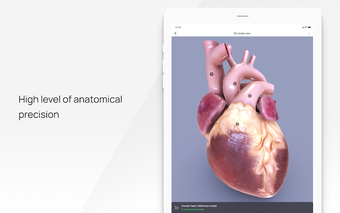

All 3D pathology models are developed in close cooperation with medical experts of hospitals and research centers. They are thought out to the very smallest detail. Each category contains models of healthy organs.

VOKA Pathology 3D is an educational tool for medical students, lecturers, and physicians. It can help you learn about human anatomy and pathology.